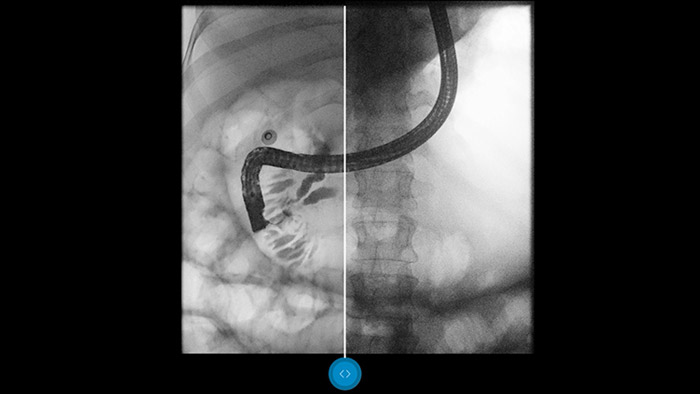

Low-dose settings are common in today’s fluoroscopic examinations. Unfortunately this leads to images with high quantum noise, adversely impacting your ability to reach a confident diagnosis. Dynamic UNIQUE’s real-time image processing capability is an innovative advantage found only in Philips radiography/fluoroscopy systems, including the ProxiDiagnost N90 and the CombiDiagnost R90. With Dynamic UNIQUE, you’ll enable better imaging outcomes and improve your diagnostic confidence.

Dynamic UNIQUE delivers superb detail visibility with real-time de-noising, from the first frame to the last. Diagnostic information for each frame is displayed with great clarity, at the correct brightness, and with very low latency. Image representation is consistent and stable, even when the image content varies rapidly. Dynamic UNIQUE supports fast and safe low-dose examinations by providing clarity of detail to improve your diagnostic confidence.

Dynamic UNIQUE features intelligent spatiotemporal noise suppression, temporal brightness stabilization, and real-time multiscale image enhancement, to permit high-quality image processing in real-time.